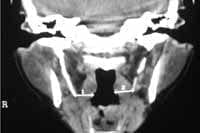

Se manejo una nueva técnica para la evaluación del proceso estiloideo: el paciente es colocado en decúbito supino con la cabeza extendida de la misma forma en que se toman las proyecciones coronales para TC de oídos, se realiza la primera proyección localizadora llamada Scout View en la cual se observa una imagen lateral del cráneo y luego se angula en el sentido anatómico de la apófisis estiloides. (Imagen 6).

Se hizo un corte de 10 mm de espesor en la región craneocervical siguiendo el eje del proceso estiloideo. Con la técnica se pretende obtener una imagen completa de los procesos estiloideos, cuando no se logra, se realizan dos o tres cortes que con el programa de reconstrucción de imágenes en los que se superponen los cortes obtenidos se identifican los procesos estiloideos. El examen dura menos de cinco minutos y la dosis de radiación es baja ya que sólo se hacen máximo tres cortes.

Es posible por medio de TAC realizar una evaluación sistemática y confiable del proceso estiloideo en cuanto a su morfología, longitud, espesor; el ángulo de la Apófisis Estiloides con respecto a la base del cráneo y la mínima distancia entre la punta del proceso estiloideo y la luz orofaríngea (Imagen 7 a 11).